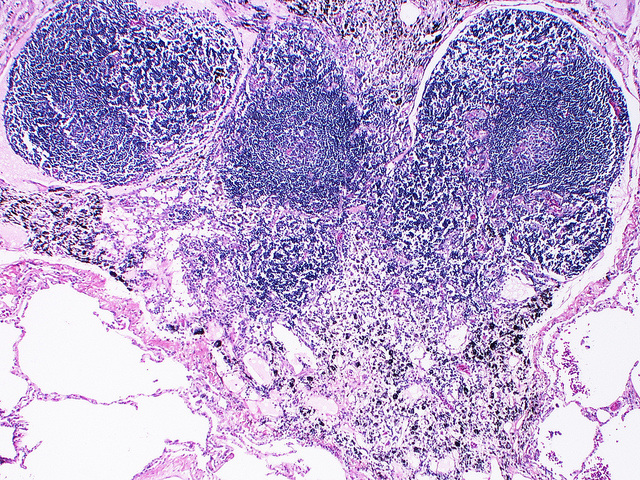

Внутрилёгочный лимфатический узел с герминативными центрами. (Фото Yale Rosen / Flickr.com.)

В герминативных центрах оседают клетки памяти, чья задача – узнавать даже ничтожные количества патогена, если он снова когда-нибудь появится. Распознавание вируса происходит с помощью белковых рецепторов на поверхности лимфоцитов. Эти рецепторы представляют собой те же антитела в комплексе с другими белками. Антитела могут быть разными, и, выставляя их из мембраны наружу, можно оценить, насколько крепко тот или иной вариант иммуноглобулинов связывает вирусный белок и, соответственно, годится ли такой иммуноглобулин для «серийного производства». В лимфатических узлах В-клетки клонируются, причём каждый клон получает случайную мутацию в рецептор. Большинство мутаций оказываются бесполезными, но попадаются среди них такие, которые усиливают взаимодействие рецептора с антигеном. Если рецептор, а значит, и антитела В-клетки оказываются достаточно эффективными при связывании чужеродной молекулы, В-лимфоцит покидает герминативный центр лимфатического узла и отправляется патрулировать организм.